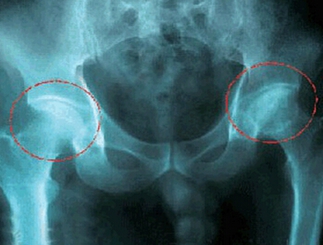

股骨頭壞死的定義是由于不同病因破壞了股骨頭的血液供應,造成了血供障礙,因缺血而使骨組織營養中斷、骨細胞死亡,以不定區域的骨小梁和骨髓壞死為特征的骨科常見病。

股骨頭壞死是骨科的一個多發疾病,導致股骨頭壞死的發病原因也是各種各樣的;我們可以簡單的歸納為兩類:

第一類分為創傷性股骨頭壞死,例如,股骨頸骨折,股骨頭骺滑脫等。很多交通事故里的患者都是因為治療不及時,或是耽誤治療而最終患上股骨頭壞死。

第二類分為非創傷性股骨頭壞死,例如,激素治療,酒精中毒,減壓病等。